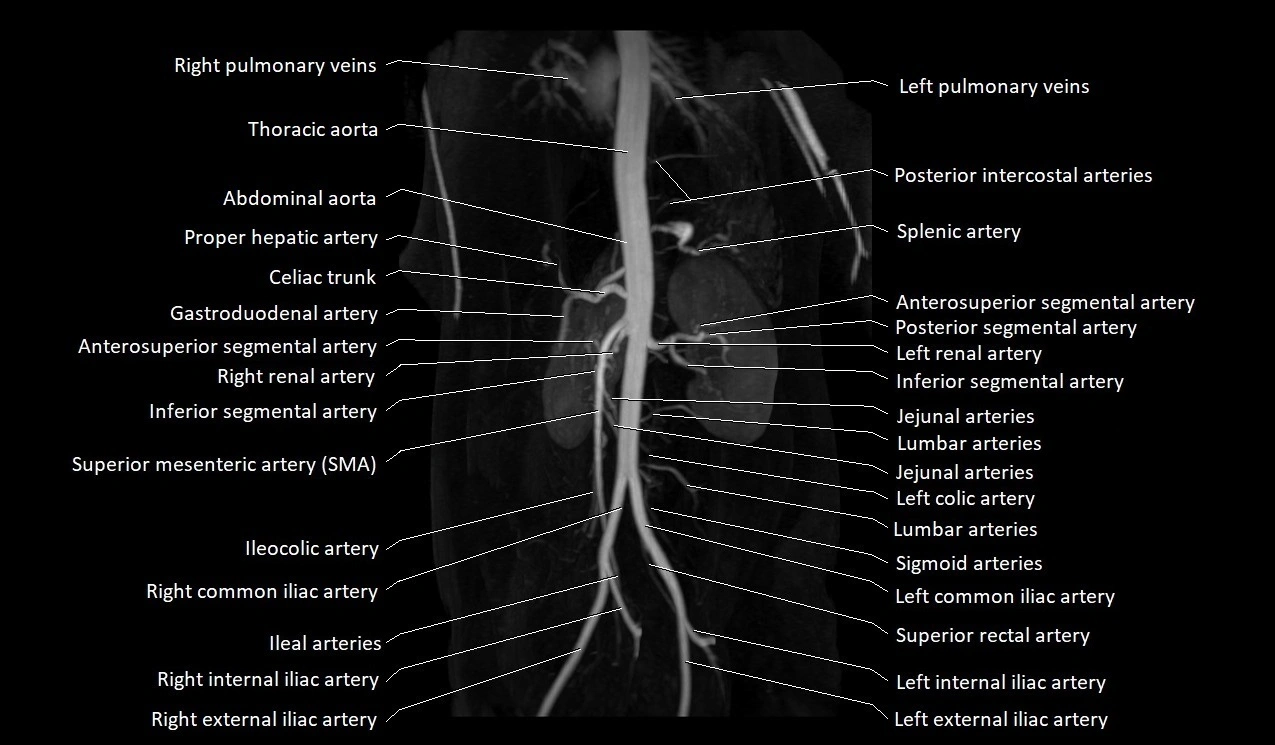

MRI images

image